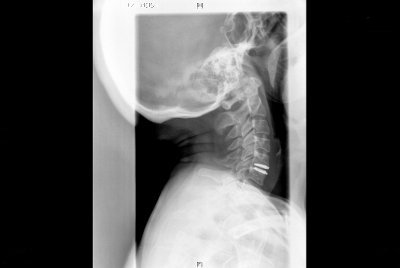

Columna cervical